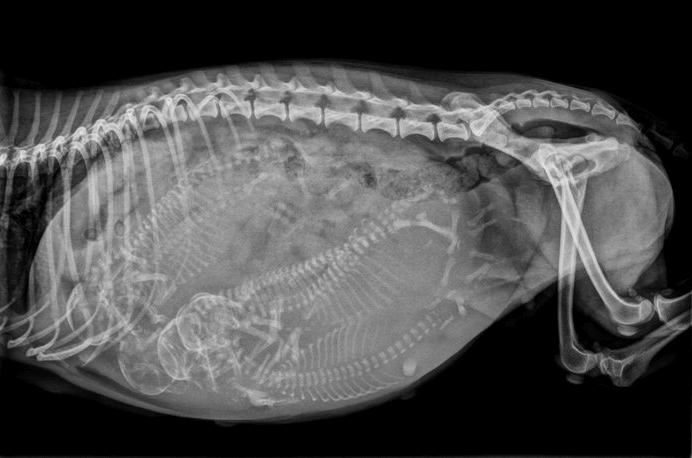

Kliniğimizin bir diğer hizmet alanı olan doğum ve jinekoloji bölümü gebelik öncesi denemden başlayarak doğum ve doğum sonrası kedi ya da köpeğimizin normal ya da anormal olarak karşılaşacağı tüm durumlar hakkında hizmet vermektedir. Jinekoloji bölümümüz ise vajinadan başlayarak rahim (uterus ve yumurtalık (ovaryum) olarak adlandırdığımız kanalın tüm hastalıklarının tanı ve tedavisi için kurulmuştur .

Detaylı İnceleKliniğimizin bir diğer hizmet alanı olan doğum ve jinekoloji bölümü gebelik öncesi denemden başlayarak doğum ve doğum sonrası kedi ya da köpeğimizin normal ya da anormal olarak karşılaşacağı tüm durumlar hakkında hizmet vermektedir.

Detaylı İnceleZoi veteriner kliniği bünyesinde kedi ve köpeklere spesifik cihazlar ile laboratuvar ve görüntüleme hizmetleri vermekteyiz. Kliniğimizde doğru tanıya gidebilmek için birçok tahlil ve tetkiklere başvurmaktayız.